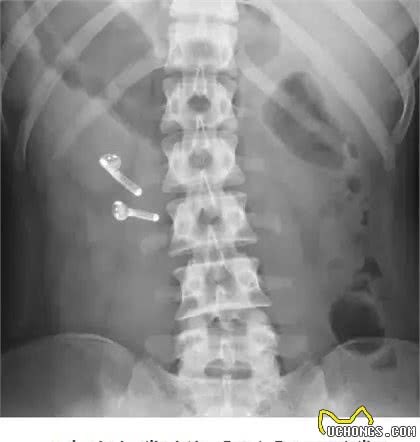

4.吞食异物

这也是便血的常见原因之一。许多狗会因为好奇而误食瓶盖、鱼线、玩具和其他异物,一些主人喜欢在自己做饭时喂狗几块骨头。这些东西在消化过程中很可能会划伤狗的肠粘膜,导致溃疡和便血。有时异物会堵塞肠道,甚至诱发肠套叠。此时,只有手术才能解决。